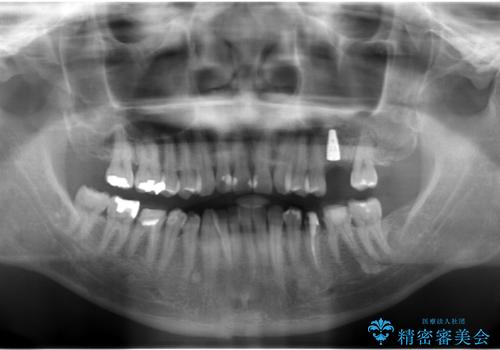

上の奥歯のインプラント、全体的な虫歯治療

- 上の奥歯が無いところにインプラントを希望して来院。

インプラントの向かい合わせの歯や隣の歯の虫歯治療も併せて行なっています。

治療の内訳

左上6:インプラント(ストローマン)20万円、カスタムアバットメント10万円、スクリューリテイン仮歯2万円、ジルコニアクラウン10万円、ソケットリフト10万円、マイナーGBR 5万円、静脈麻酔(麻酔認定医)5万円

左上7・左下7:PGAインレー 各6万円

左下5:仮歯 1万円、ジルコニアクラウン10万円、ファイバーコア 2万円

左下6:仮歯1万円、ジルコニアクラウン10万円

クラウンは全てスタンダードです。